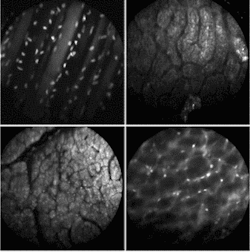

So far, Gmitro and his colleagues have experimented with using the instrument in two ways—catheter-based imaging in the standard endoscopy arena and bare fiber through a biopsy needle. In the first approach, they have focused on imaging in the GI tract, the ovaries, and other peritoneal tissues via a small incision in the abdomen (see Fig. 4). In the bare-fiber approach, they have started some work in brain biopsies. In both cases, the group has opted to take a fluorescence-rather than reflectance-based approach.

FIGURE 4. Multispectral fluorescence confocal microendoscopy offers the ability to do disease-specific imaging in real time using different phorofluors. Acridine orange (AO) is used extensively in multispectral experiments because of its dual emission peaks. Shown above are: in vivo image of the abdominal wall of a mouse, topical staining with SYTO 16 (upper left); in vivo image of surface of rat kidney, topical staining with AO (upper right); in vivo image of surface of rat liver, topical staining with AO (lower left); in vivo image of the retroperitoneum of a mouse, topical staining with AO (lower right),